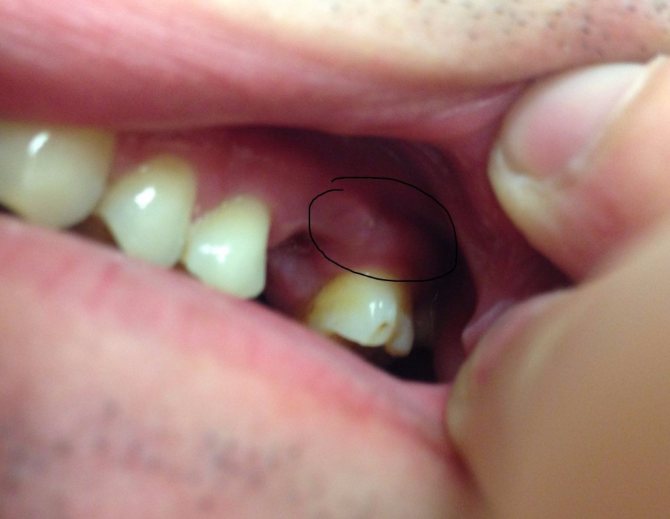

Гигантоклеточный

Образуется из остеогенных клеток и располагается всегда на альвеолярном гребне, закрывая постепенно собой коронки. Опухоль плотная, достаточно упругая, округлая, буро-коричневого цвета, растет медленно, но ее разрастания могут достигать объемов, нарушающих симметричность лица.

В единичных случаях проявляет болезненность, а при пальпации дает непродолжительное кровотечение. В зоне ее присутствия зубы расшатываются.

Различают 2 ее вида:

- Центральная – развивается из челюстной кости.

- Периферическая – возникает из мягких десневых тканей.

Патология в основном развивается у людей старшего возраста (после 40 лет), причем, чаще диагностируется у женщин.